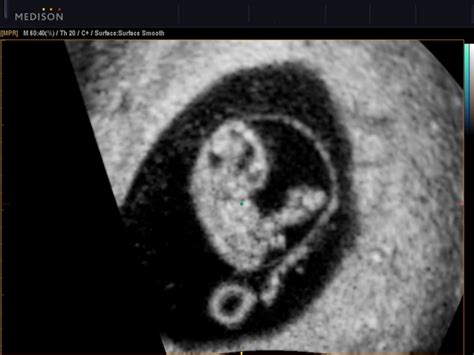

What To Expect At 8 Week Scan / 5 Weeks Pregnant: What to Expect | Everyday Mommy : At eight weeks you will normally see a sack, a fetal pole and a heart beat.. Your first ultrasound will usually occur between 8 and 14 weeks to listen for a heartbeat to confirm that you're pregnant and to estimate a due date. The 20 week anatomy scan is a pivotal time in the pregnancy of your child. Xx 0 like sarah w (62) You'll probably have missed your second period. Eight weeks into a pregnancy is the most common time to have a first ultrasound, also called the dating scan, as one of the main purposes is to determine gestational age.

Little bean shape, head end fattest with tiny buds of arms and legs and a little heartbeat. What are they looking for during the first ultrasound? Baby measured 11mm at the first, 13mm at the second. In many countries, the first scan of a pregnant woman takes place between weeks 8 and 14. 8 week scan kmspeer720 measuring 3 days ahead and a perfect 170 heartbeat.

8 week scan kmspeer720 measuring 3 days ahead and a perfect 170 heartbeat. A good hcg level will peak at 8 to 12 weeks of pregnancy, and then slowly decline until it reaches a lower level. If you are having a scan around 9 weeks, it will normally be a transvaginal scan (tvs). At an 8 week scan, it's possible to see the embryo's development, especially their big head and small body. At 8 weeks you will see the gestational sac, a fetal pole and yolk sac and a heartbeat flickering away.